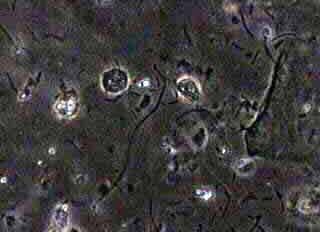

Σε μιά αντικειμονοφόρο πλάκα τοποθετούμε μιά σταγώνα φυσιολογικού ορού. Με μια ψήκτρα λαμβάνουμε μικρό δείγμα κολπικού εκκρίματος, το ανακατεύουμε με τον φυσιολογικό ορό, τοποθετούμε μία καλυπτρίδα και το εξετάζουμε αμέσως με κοινό μικροσκόπιο, σε μεγεθύνσεις 10Χ10 και 10Χ40, με στενή δέσμη φωτός, δηλαδή με κλειστό το διάφραγμα του μικροσκοπίου. Αν υπάρχει δυνατότητα για αντίθετες φάσεις φωτός, οι εικόνες είναι καλλίτερες. Γενικά όμως επαρκεί και ένα απλό μονοφθάλμιο μικροσκόπιο.

Εύκολα διακρίνουμε τα γνωρίσματα της μυκητιάσεως:

Κατ' αρχήν υπάρχει φυσιολογική χλωρίδα (γαλακτοβάκιλλος Doederlein.)

Περ' απ΄αυτόν, μπορεί να διαπιστώσουμε κάποιο ή περισσότερα από τα παρακάτω ευρήματα:

Ψευδομυκητήλια και ενδεχομένως χλαμυδοσπόρια.

Σπόρους σε μέγεθος περίπου ερυθροκυττάρων (Candida albicans) ή και σπόρους πολυ μικρότερους του ερυθρoκυττάρου (Candida glabrata)

Nωπά παρασκευάσματα σε κολπίτιδα εκ μονιλιάσεως.